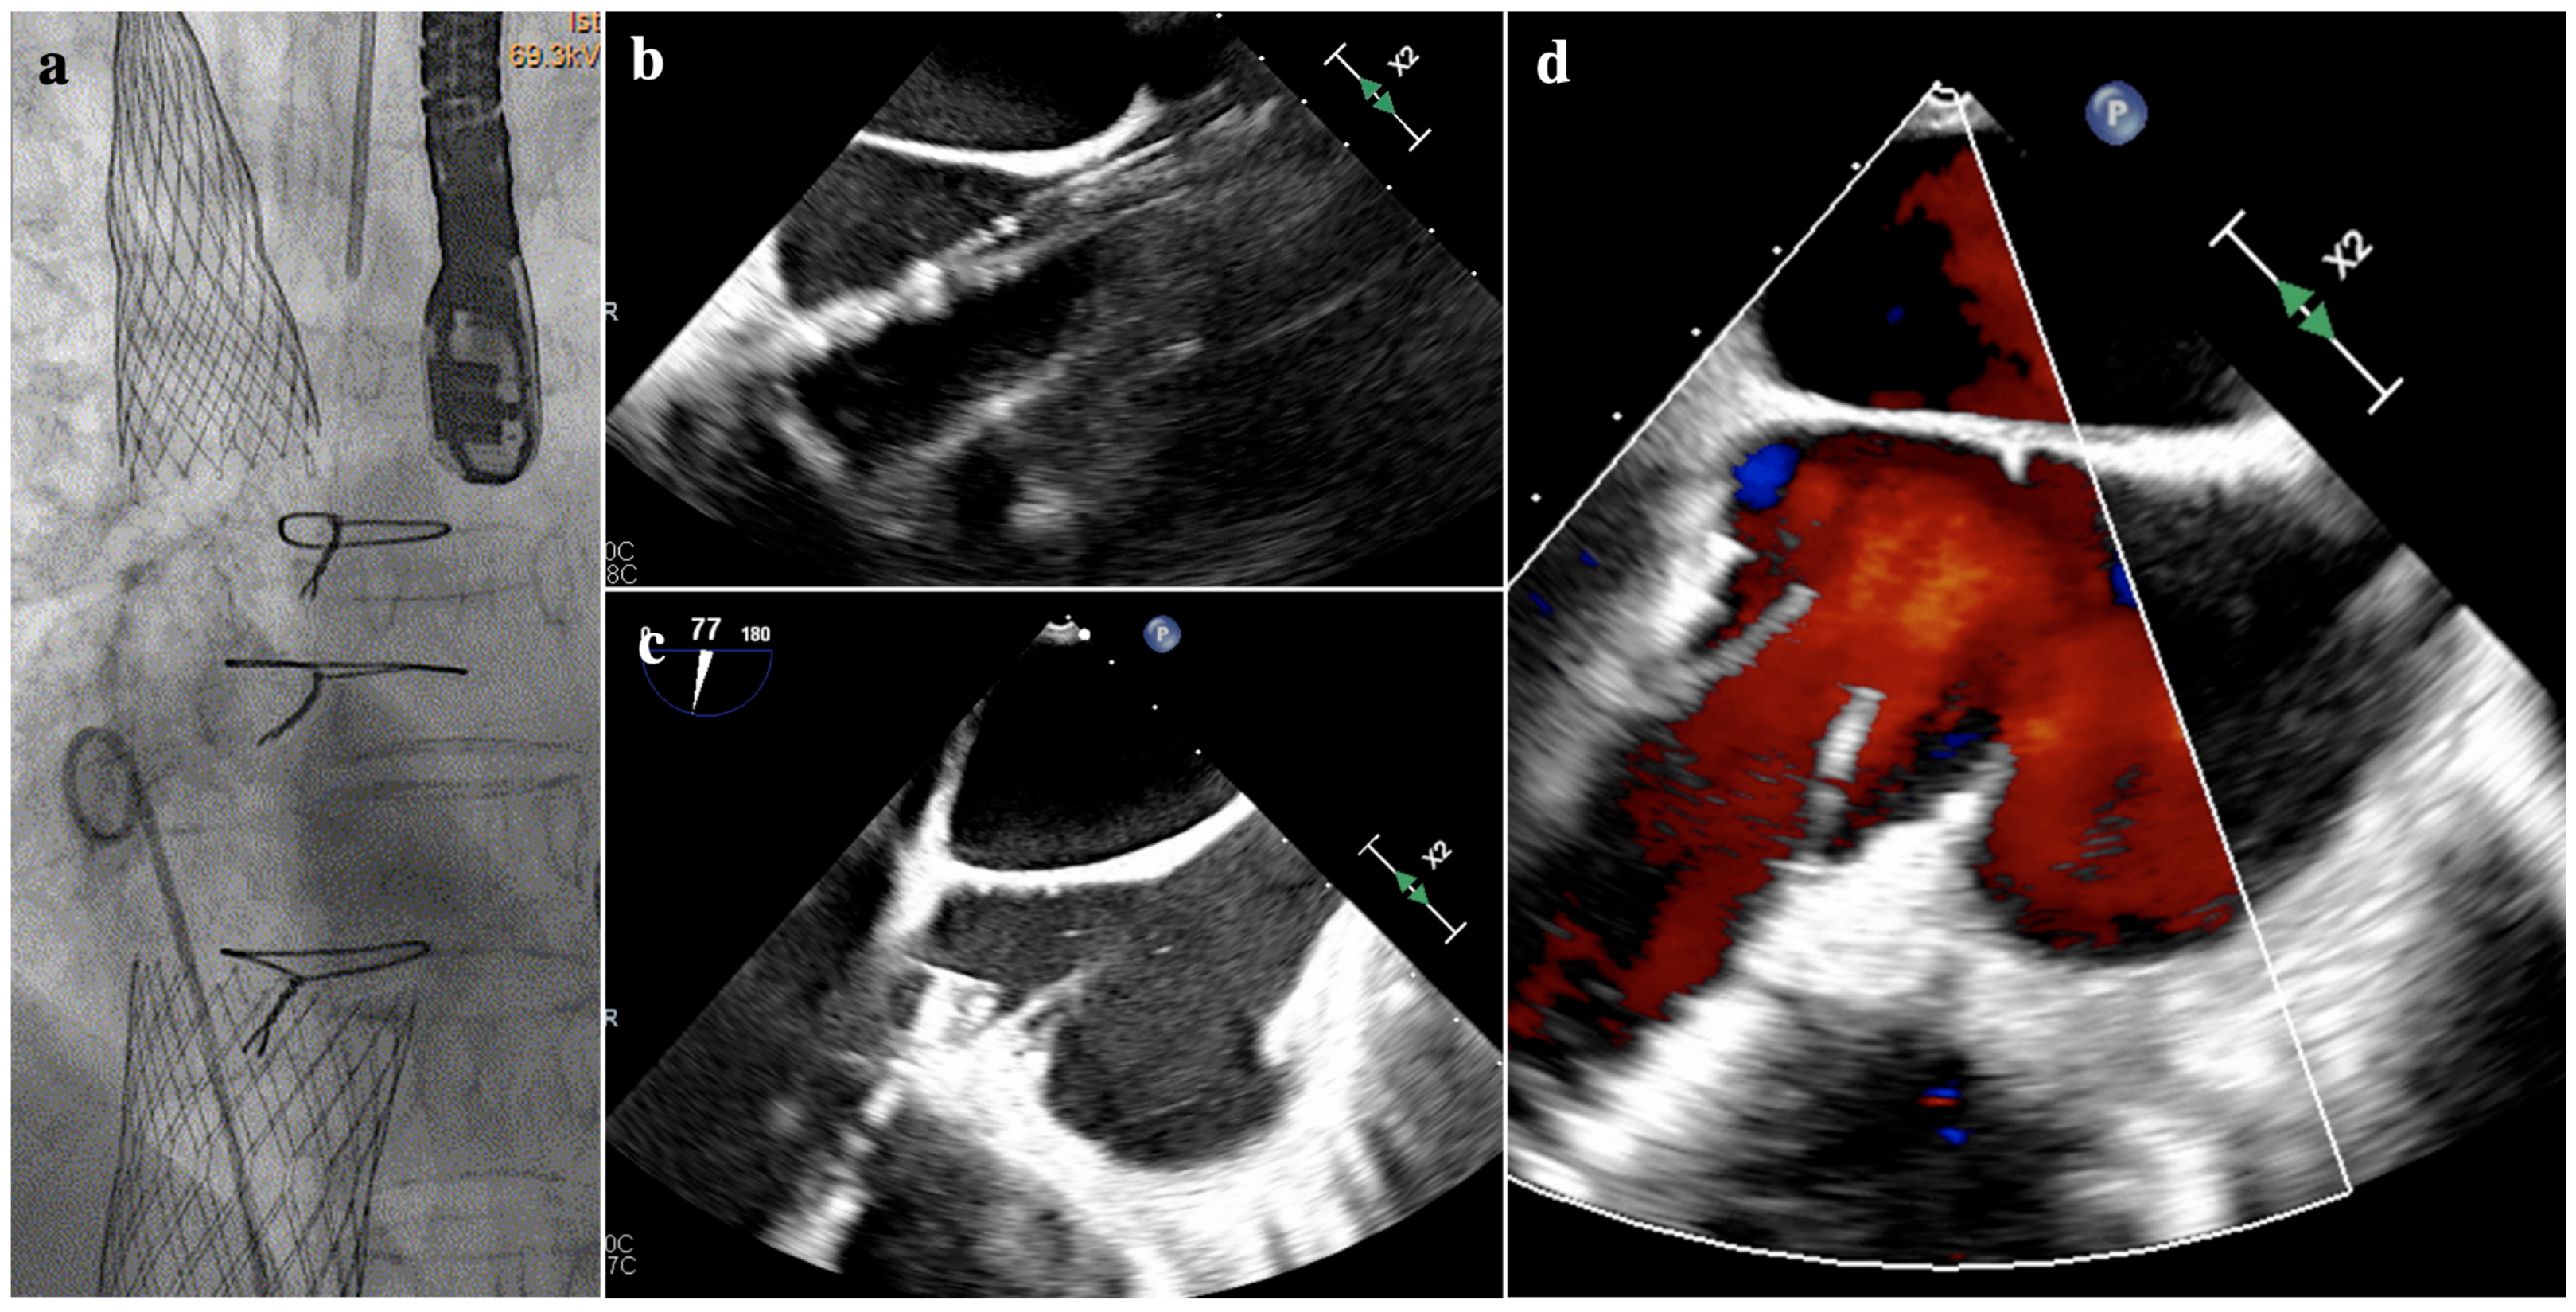

3.2.2. The Cardiovalve System

- RA height: the height is calculated from the TV plane. The minimum cutoff is 60 mm to make the valve positioning feasible and to minimize the risk of complications during the advancement of the delivery system.

- RV length: the minimal distance between the apex of the RV and the tricuspid annular plane is 45 mm in diastole. Below the proposed cutoff, diving of the valve in the ventricle is not feasible.

- IVC offset and top distance: describes the distance and angular relationship between the entry point of the IVC into the RA and the TV annulus. This anatomical detail is crucial for the precise alignment of the delivery system with the TV annulus, for the trajectory and final positioning of the device. An offset less than 20 degree in diastole is usually favourable. The IVC top distance refers to the vertical distance from the superior aspect (or top) of the IVC to the TV annulus and it should be at least 50 mm to have a correct insertion depth and trajectory.

- Annulus diameters: minimal annulus diameter should be above 36 mm. Moreover, the shape of the annulus should not be too oval to avoid device mismatch. Cardiovalve has 3 different sizes that cover a broad range of diameters (45–55 mm).